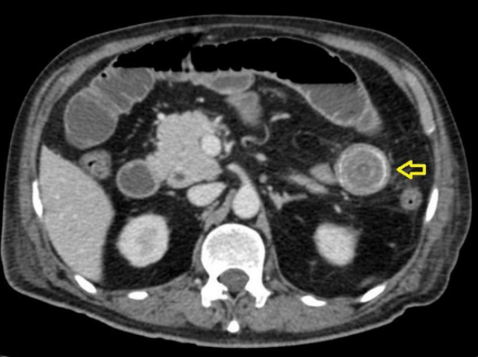

En dicha institución se revalora al paciente, evidenciando al examen físico mal estado general, consciente, orientado, con signos de dificultad respiratoria y desaturación al aire ambiente hasta 70%, saturación hasta 92% con oxígeno por máscara con reservorio a 8 l/min, piel y mucosas moderadamente secas, normocoloreadas, pulmones con murmullo vesicular disminuido con estertores y roncus diseminados en ambos campos pulmonares, abdomen levemente distendido, con ruidos hidroaereos (+) hipoactivos, blando, doloroso a la palpación profunda en mesogastrio, sin datos de irritación peritoneal, tacto rectal con esfínter normotónico, ampolla rectal vacía y dedo de guante explorador limpio, siendo el resto del examen conservado. Se obtienen estudios complementarios de laboratorios en sangre que reportan: leucocitosis de 10 640/ml, con neutrofilia del 88 %, Hb 12 g/dl (previo de 15,2), normocítica, normocrómica, Hto 34,8 %, hipoproteinemia con hipoalbuminemia severa con proteínas totales de 4,2 g/dl y albumina de 2,1 g/dl, e hipokalemia leve con K de 3,0 mEq/L, además de gasometría arterial que evidenciaba alcalosis metabólica parcialmente compensada con acidosis respiratoria, con insuficiencia respiratoria aguda hipoxémica moderada (PaFiO2 170), y resto de laboratorios del hemograma, coagulograma, glicemia, pruebas renales y hepatograma dentro de parámetros normales. Se obtiene a la vez Rx de tórax PA y abdomen AP de pie, evidenciando en el primero imágenes radiopacas de infiltrado alveolo-intersticial diseminadas en ambos campos pulmonares a predominio del lado izquierdo, y en la segunda, asas de intestino delgado dilatadas con imagen sugestiva de pila de monedas y niveles hidroaéreos a predominio del lado izquierdo (Figura 1). Tras la obtención de estos exámenes y en el contexto del paciente se han tomado en cuenta los diagnósticos diferenciales de obstrucción intestinal vs hemorragia digestiva alta, este último según la institución inicial que realizó la referencia, que indicaba la presencia de vómitos porráceos y el evidente descenso de la Hb en 3 puntos, por lo que se continúa con la indicación de endoscopia digestiva alta la cual reporta: “Datos de obstrucción intestinal alta (debito de retención proveniente de segunda y tercera porción duodenal) (Figura 2), sospecha de metaplasia columnar de esófago, gastritis crónica superficial de antro, estudio parcialmente satisfactorio (por segmentos con debito retentivo no valorables)”. Con estos hallazgos se refuerza mucho más la primera hipótesis, pero llama la atención que un paciente sin antecedentes quirúrgicos abdominales presente datos de obstrucción intestinal, además de tratarse de un paciente con un cuadro clínico atípico, y que al momento no había podido ser resuelto bajo medidas conservadoras, por lo que se decide solicitar estudios ampliados extrainstitucionales, como una tomografía axial computarizada (TAC) de abdomen con contraste de forma urgente; tras gestionar la misma, se obtiene reporte que indica (Figuras 3 y 4): “Hallazgos tomográficos compatibles con íleo biliar (imagen de cálculo de 4 x 3,2 cm con áreas de calcificación en su pared a nivel de yeyuno proximal), probable fístula bilio-digestiva (colecistoduodenal), neumobilia, pequeños quistes renales simples bilaterales, hallazgos de la porción valorable de tórax sugerente de proceso infeccioso de etiología viral sugestivas de COVID-19”. Con ello se solicita la valoración por el servicio de cirugía que, en misma fecha de ingreso, realiza procedimiento quirúrgico de laparotomía exploradora, enterotomía, extracción de cálculo y enterorrafia, con diagnóstico postoperatorio de “Obstrucción intestinal alta, íleo biliar, neumonía por SARS-COV2, hiperplasia prostática”, describiendo en los hallazgos operatorios un cálculo de aproximadamente 4 x 4 cm que ocupaba la totalidad de la luz yeyunal a +/- 60 cm del ángulo de Treitz.

En relación a los hallazgos imagenológicos, la imagen en pila de monedas sigue teniendo alto valor diagnóstico en patologías obstructivas del intestino delgado como es en el caso nuestro, al igual que menciona Carpio-Deheza G5 en su publicación de abdomen agudo quirúrgico. En mención a imagenología se recomienda una adecuada valoración de los estudios iniciales que en sospecha de íleo biliar podrían ayudar al diagnóstico y evidenciar la conocida Triada de Rigler, que hace mención de la conjunción en la radiografía de abdomen de pie de: neumobilia, asas de intestino delgado dilatadas y la visualización directa o indirecta de un cálculo en intestino delgado, y en ocasiones, el cambio de posición del lito en radiografías de control. En la revaloración del caso de nuestro paciente se evidencia dos de estos signos específicos, asas de intestinos delgado dilatadas y una tenue imagen sugerente de neumobilia, siendo el hallazgo de dos de los signos de la triada de Rigler patognomónicos de íleo biliar según Aguila-Gomez MV; es así, que el uso de ésta puede ayudar y prescindir de elementos no coste-accesibles en algunos casos8.